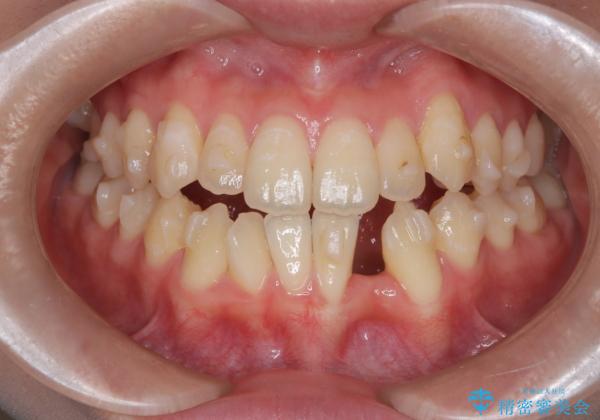

- 他院でインビザライン矯正を行っていたものの、通院先の閉院により治療が継続できなくなったとのことで来院されました。

診査の結果、すでに下顎前歯の抜歯が行われていましたが、マウスピースの適合が著しく悪くなっており、歯が計画通りに動いていない状態でした。また、歯を支える骨の厚みや歯肉の薄さを考慮すると、このままマウスピースによる傾斜移動を続けるのは歯肉退縮(歯茎が下がること)のリスクが非常に高いと判断。

安全かつ確実に抜歯スペースを閉じ、咬み合わせを完成させるため、マウスピースから**ワイヤー矯正(マルチブラケット装置)**へ切り替えるリカバリープランを提案しました。